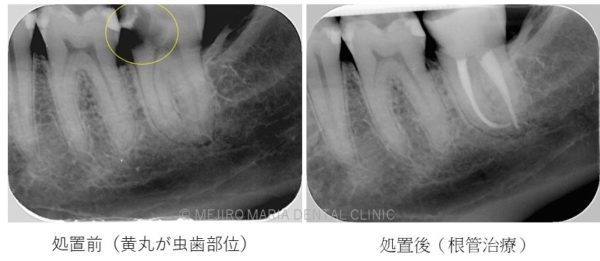

C3について

歯髄まで虫歯が到達してしまっている場合、何かしらの歯髄への処置が必要となります。歯髄の病気の進行は、

歯髄壊死

歯髄壊死は歯髄に血流がなく、ほぼ全ての歯髄が細菌感染により壊死し、根尖性歯周炎という炎症が根尖まで波及してしまっている状態です。この場合、適切な根管治療を行うことが必要となります。根管治療を行っても治癒に至らない症例に関しては歯根端切除術が必要になります。

根管治療